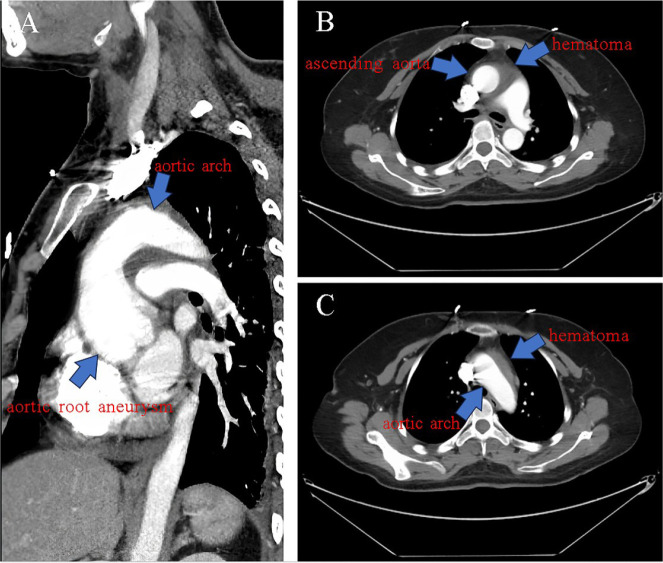

Pregnancy-related aortic dissection is an uncommon and serious condition since it poses a risk to the lives of both the mother and the fetus. Here, we describe a pregnant woman who suffered from aortic dissection twice during the same pregnancy and whose fetus was safely delivered following aortic root replacement and thoracic aortic stent-graft implantation.